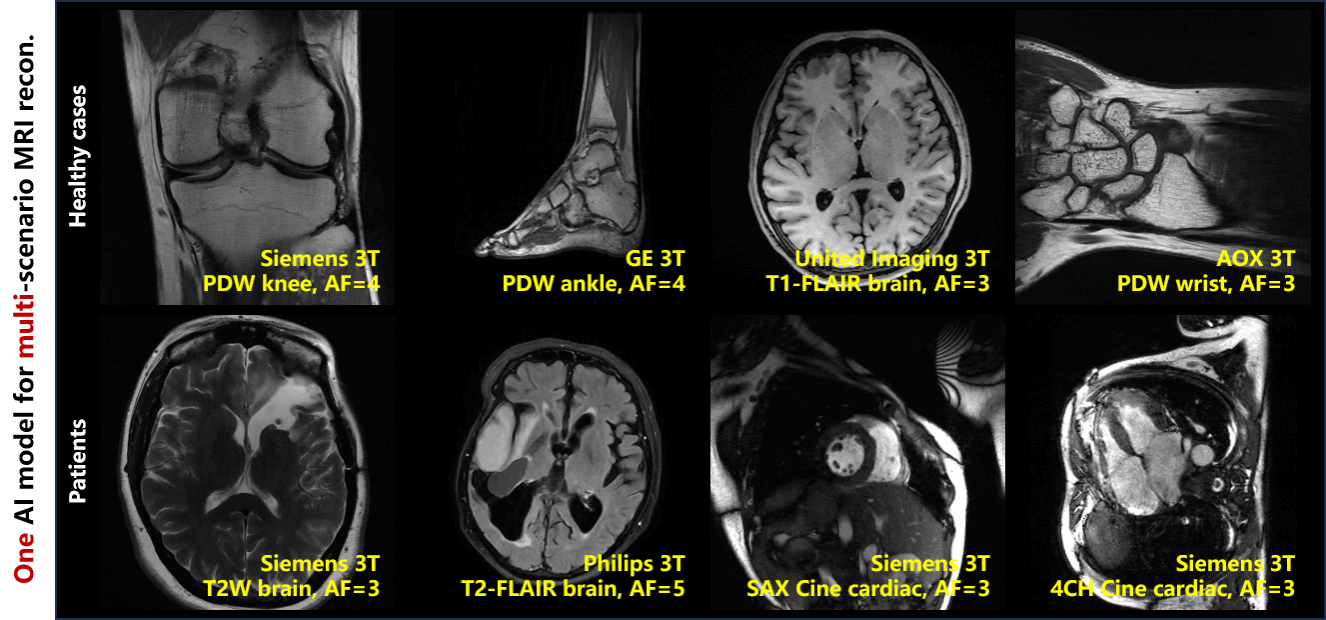

通过物理生成数据和降维学习,解决了大规模人体数据采集难的问题,显著降低了深度学习对实测数据的依赖(高达96%),仅用一个训练好AI,毫秒级高质量重建 5家设备商、7个扫描中心、5种解剖结构、6种对比度、4种快速采样图像,在临床2种神经疾病、1种心血管疾病的患者数据表现出很好适应性,10位医生的图像盲评4.3/5分(Excellent:4~5)。该工作有望为MRI泛化学习提供新路径。

图2 仅用一个AI模型,可实现多场景MRI的高质量泛化重建